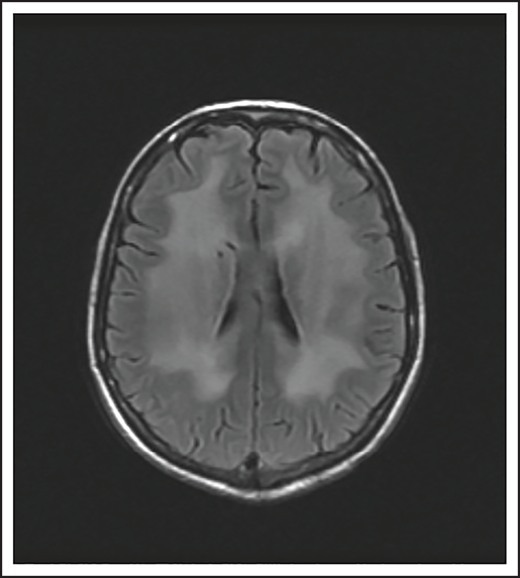

A 74-year-old man with a history of DLBCL treated with R-CHOP presented with progressive confusion and right-side weakness. A brain MRI demonstrated a contrast-enhancing lesion in the corpus callosum with extension into the left parietal region. A biopsy of the enhancing lesion confirmed a diagnosis of DLBCL. No other sites of disease were identified, and he was diagnosed with isolated CNS relapse. He was treated with HD-MTX, rituximab, and temozolomide for 4 cycles, and he achieved a complete radiographic response. Three years later, he presented with progressive memory loss, urinary incontinence, and gait ataxia. A brain MRI demonstrated periventricular white matter T2/FLAIR hyperintensities (Figure 3). Evaluation for toxic and metabolic causes of his symptoms was negative. His diagnosis was MTX-induced leukoencephalopathy.

Brain MRI of a patient with leukoencephalopathy caused by use of HD-MTX. An axial T2 fluid attenuated inversion recovery (FLAIR) image shows periventricular hyperintense signal reflecting leukoencephalopathy.

HD-MTX as well as IT MTX can cause acute as well as subacute encephalopathy.57,58 Acute encephalopathy is usually reversible. Subacute, or chronic, encephalopathy, as seen in case 4, is typically progressive, irreversible, and associated with high morbidity and mortality. It is a diagnosis of exclusion and as described in case 4, other causes must be excluded. The risk is higher with older age and when combined with whole-brain radiation therapy (WBRT).59